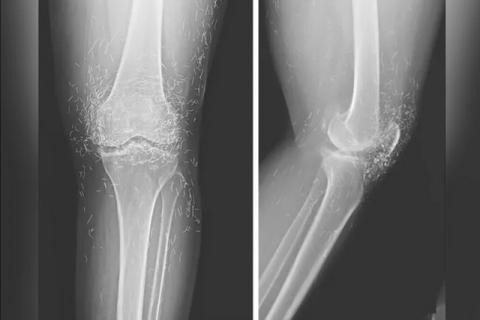

اما این روش هم نه‌تنها دردی از این زن دوا نکرد، بلکه زانودرد او را هم شدت بخشید. درنهایت او مجبور شد دوباره به بیمارستان مراجعه کند و پزشکان هنگام تصویربرداری از زانوها و دست‌های او متوجه صدها رشته‌ ریز و نازک از طلا در بافت‌های اطراف زانو و دست‌های این زن شدند.